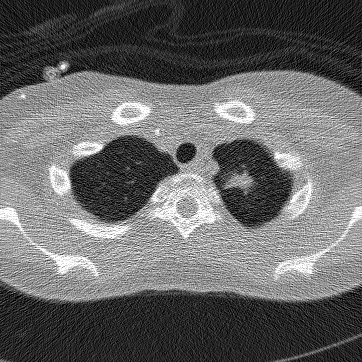

Refer to caption

(a) Original CT scan

(b) Poisson noise

Figure 5: Here N0=4×103subscript𝑁04superscript103N_{0}=4\times 10^{3} to emphasize streak artifacts introduced by the Poisson noise. For our experiments, we use N0=4×1035subscript𝑁04superscript1035N_{0}=4\times 10^{35} which is imperceptible.